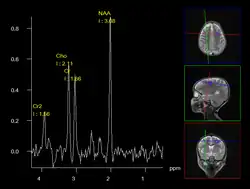

MR spectroscopy (MRS) of the brain to identify different chemical components based on their unique resonant frequencies.

A less intrusive alternative imaging technique is magnetic resonance spectroscopy (MRS), which is used to determine the chemical compositions of cells. However, it is not as reliable as biopsies.[12]